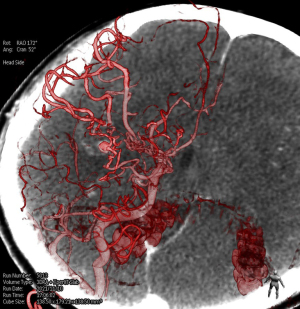

Detailed method

Preoperative CT three-dimensional angiography was performed, and the relevant original images were transferred to the Stealth Station. The three-dimensional images of the patient's skull, cerebral cortex, aneurysm, and other anatomical structures were then reconstructed, and the neurosurgeon designed the surgical plan based on the three-dimensional angiography. At the same time, the position was placed according to the lesion site during the operation. The incisions, bone flap ranges, and surgical paths were designed based on the location of the aneurysm shown by neuronavigation. The aneurysms were clipped intraoperatively under the guidance of neuronavigation. The fluorescence contrast confirmed that the aneurysm was not visible, and the surgery was concluded (Figures 1,2).